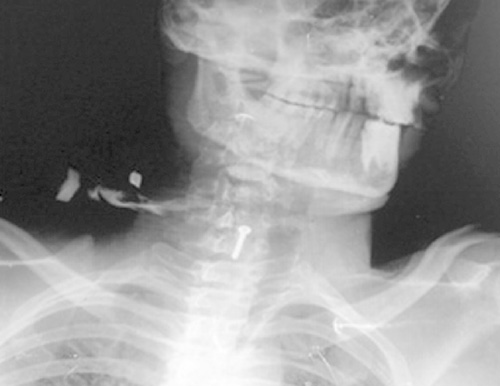

Whole Digital Body X-rays

X-rays can be used to image every part of the body and are used most commonly to look for fractures. They are also commonly used to examine the chest, abdomen, and superficial soft tissues. X-rays can identify many different conditions, and they are often a fast and easy method for your doctor to make a diagnosis.